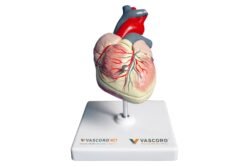

Modelo anatómico del corazón

Peana corazón